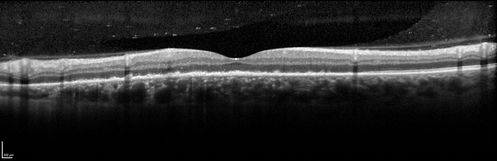

Syphillitic Optic Neuropathy and Maculopathy

46 year old woman with 2 weeks of vision loss OD.  VA 20/200 OD; 20/20 OS.  there are posterior vitreous cells on OCT in both eyes.  ICG, FAF, and FA show an abnormal macula OD.  VA improved to 20/30 within a month with treatment with PCN.